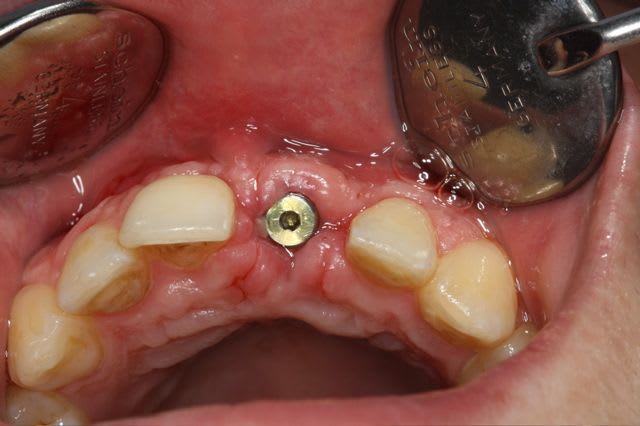

dépose des vis et pose de l'implant à 5mois1/2 avec un cj roulé et mise en place de la vis de cica,

et 3 mois 1/2 après empreinte

15j après essayage pilier et biscuit, visite au labo pour "finition en bouche" et 3 h après scellement.

le liseré visible en cervicale n'est pas le pilier mais le petit suintement dut à la sonde pour enlever les excès de ciment